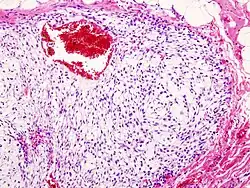

| Histopathologic image of chondrosarcoma of the chest wall. Surgical resection of recurrent mass. H & E stain. | |

Imaging studies – including radiographs ("x-rays"), computerized tomography (CT), and magnetic resonance imaging (MRI) – are often used to make a presumptive diagnosis of chondrosarcoma.[9] However, a definitive diagnosis depends on the identification of malignant cancer cells producing cartilage in a biopsy specimen that has been examined by a pathologist. In a few cases, usually of highly anaplastic tumors, immunohistochemistry (IHC) is required.